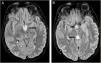

Encefalopatía de Wernicke

Wernicke's encephalopathy